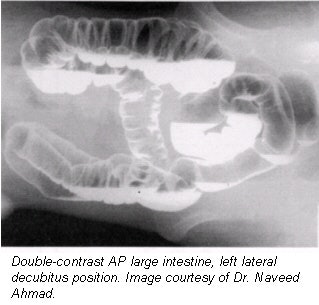

- Overhead films. All overhead films must be taken at 110 kVp; additional air should be insufflated before taking decubitus projections (approximately 5-7 pumps before each decubitus). No post-evacuation film is needed. All overhead films are obtained with the table horizontal. Suggested films that should be obtained are:

- PA to include rectum (14 x 17-inch, or 36 x 40-cm IR).

- 15º RAO with 35º tube angle caudad for sigmoid (14 x 17-inch, or 36 x 40-cm IR); three overhead films and five on a gurney against an upright bucky.

- Left lateral decubitus (14 x 17-inch, or 36 x 40-cm IR).

- Right lateral decubitus (14 x 17-inch, or 36 x 40-cm IR).

- Cross-table lateral rectum with patient prone and tip removed.

- Upright abdomen (14 x 17-inch, or 36 x 40-cm IR).